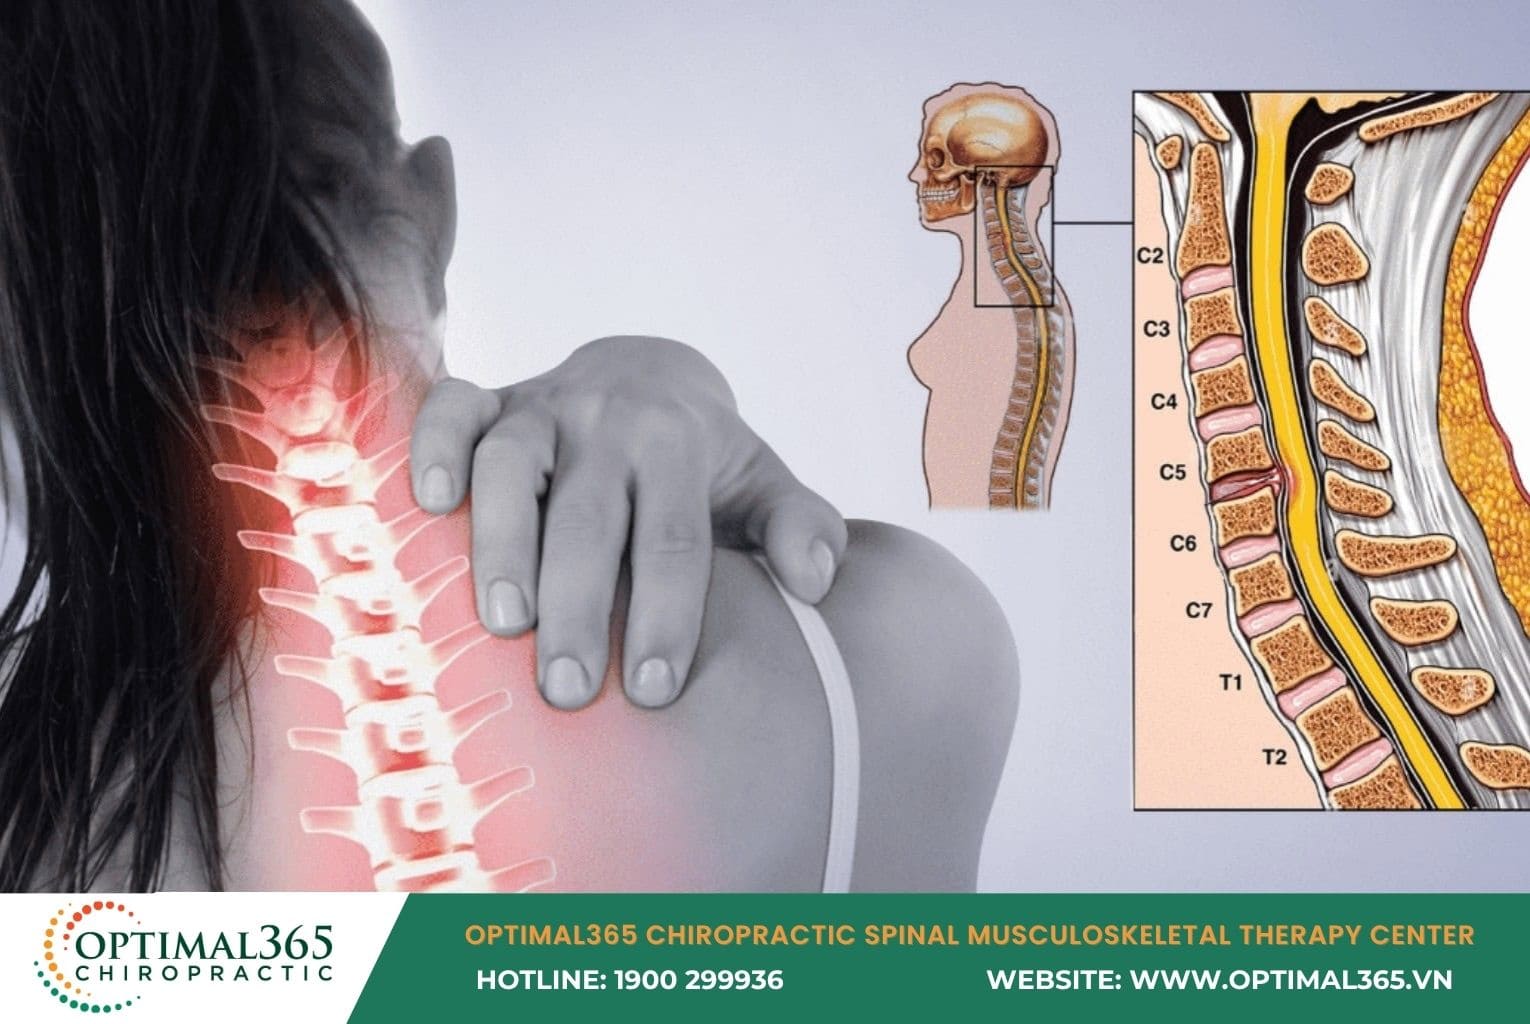

Cervical herniated disc occurs when the nucleus pulposus escapes its normal position, compressing nerve roots or the spinal cord, leading to pain, tingling, and weakness. If left untreated seriously, the condition can worsen, even causing permanent paralysis. So, what are the causes, symptoms, complications, and treatments for cervical herniated disc? Let’s explore in detail with Optimal365 Chiropractic in this article.

Structure of Cervical Spine and What is Cervical Herniated Disc?

The cervical spine consists of 7 vertebrae: C1, C2, C3, C4, C5, C6, C7, connected by intervertebral discs, slightly curved in a C-shape. Each disc acts like a “rubber cushion” with a jelly-like nucleus pulposus in the center and a fibrous annulus outside, absorbing shocks and enabling spinal flexibility.

Inside the disc, the nucleus pulposus (gel-like structure) contains proteoglycans, surrounded by a circular fibrous annulus mainly made of collagen fibers. Finally, endplates between the cartilage and vertebral body protect the surface, preventing the nucleus from being compressed inward.

Cervical herniated disc happens when the disc ages, tears, or suffers trauma. At this point, the nucleus pulposus protrudes from the annulus, compressing nerve roots or the spinal cord, causing pain and various symptoms.

Cases with multiple discs herniating simultaneously lead to multi-level cervical herniated disc, with higher complication risks. Here, pressure on the spine is much greater than in single-level herniation.